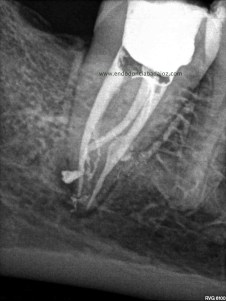

Sistemas de Conductos de un 4.7

Nos remiten a  la clínica una pieza 4.7, con necrosis pulpar y afectación periodontal, periodontitis apical:

La anatomía de los conductos nos hacia sospechar de un caso algo más complicado. Lo más complicado fue mantener la permeabilidad de los conductos. Instrumentamos con sistema rotatorio de Mtwo, mucha irrigación, se usó Irrisafe en los últimos lavajes, y como sistema de obturación usamos Condensación vertical con ola contínua, haciendo un backfilling con la Pistola Obtura II.